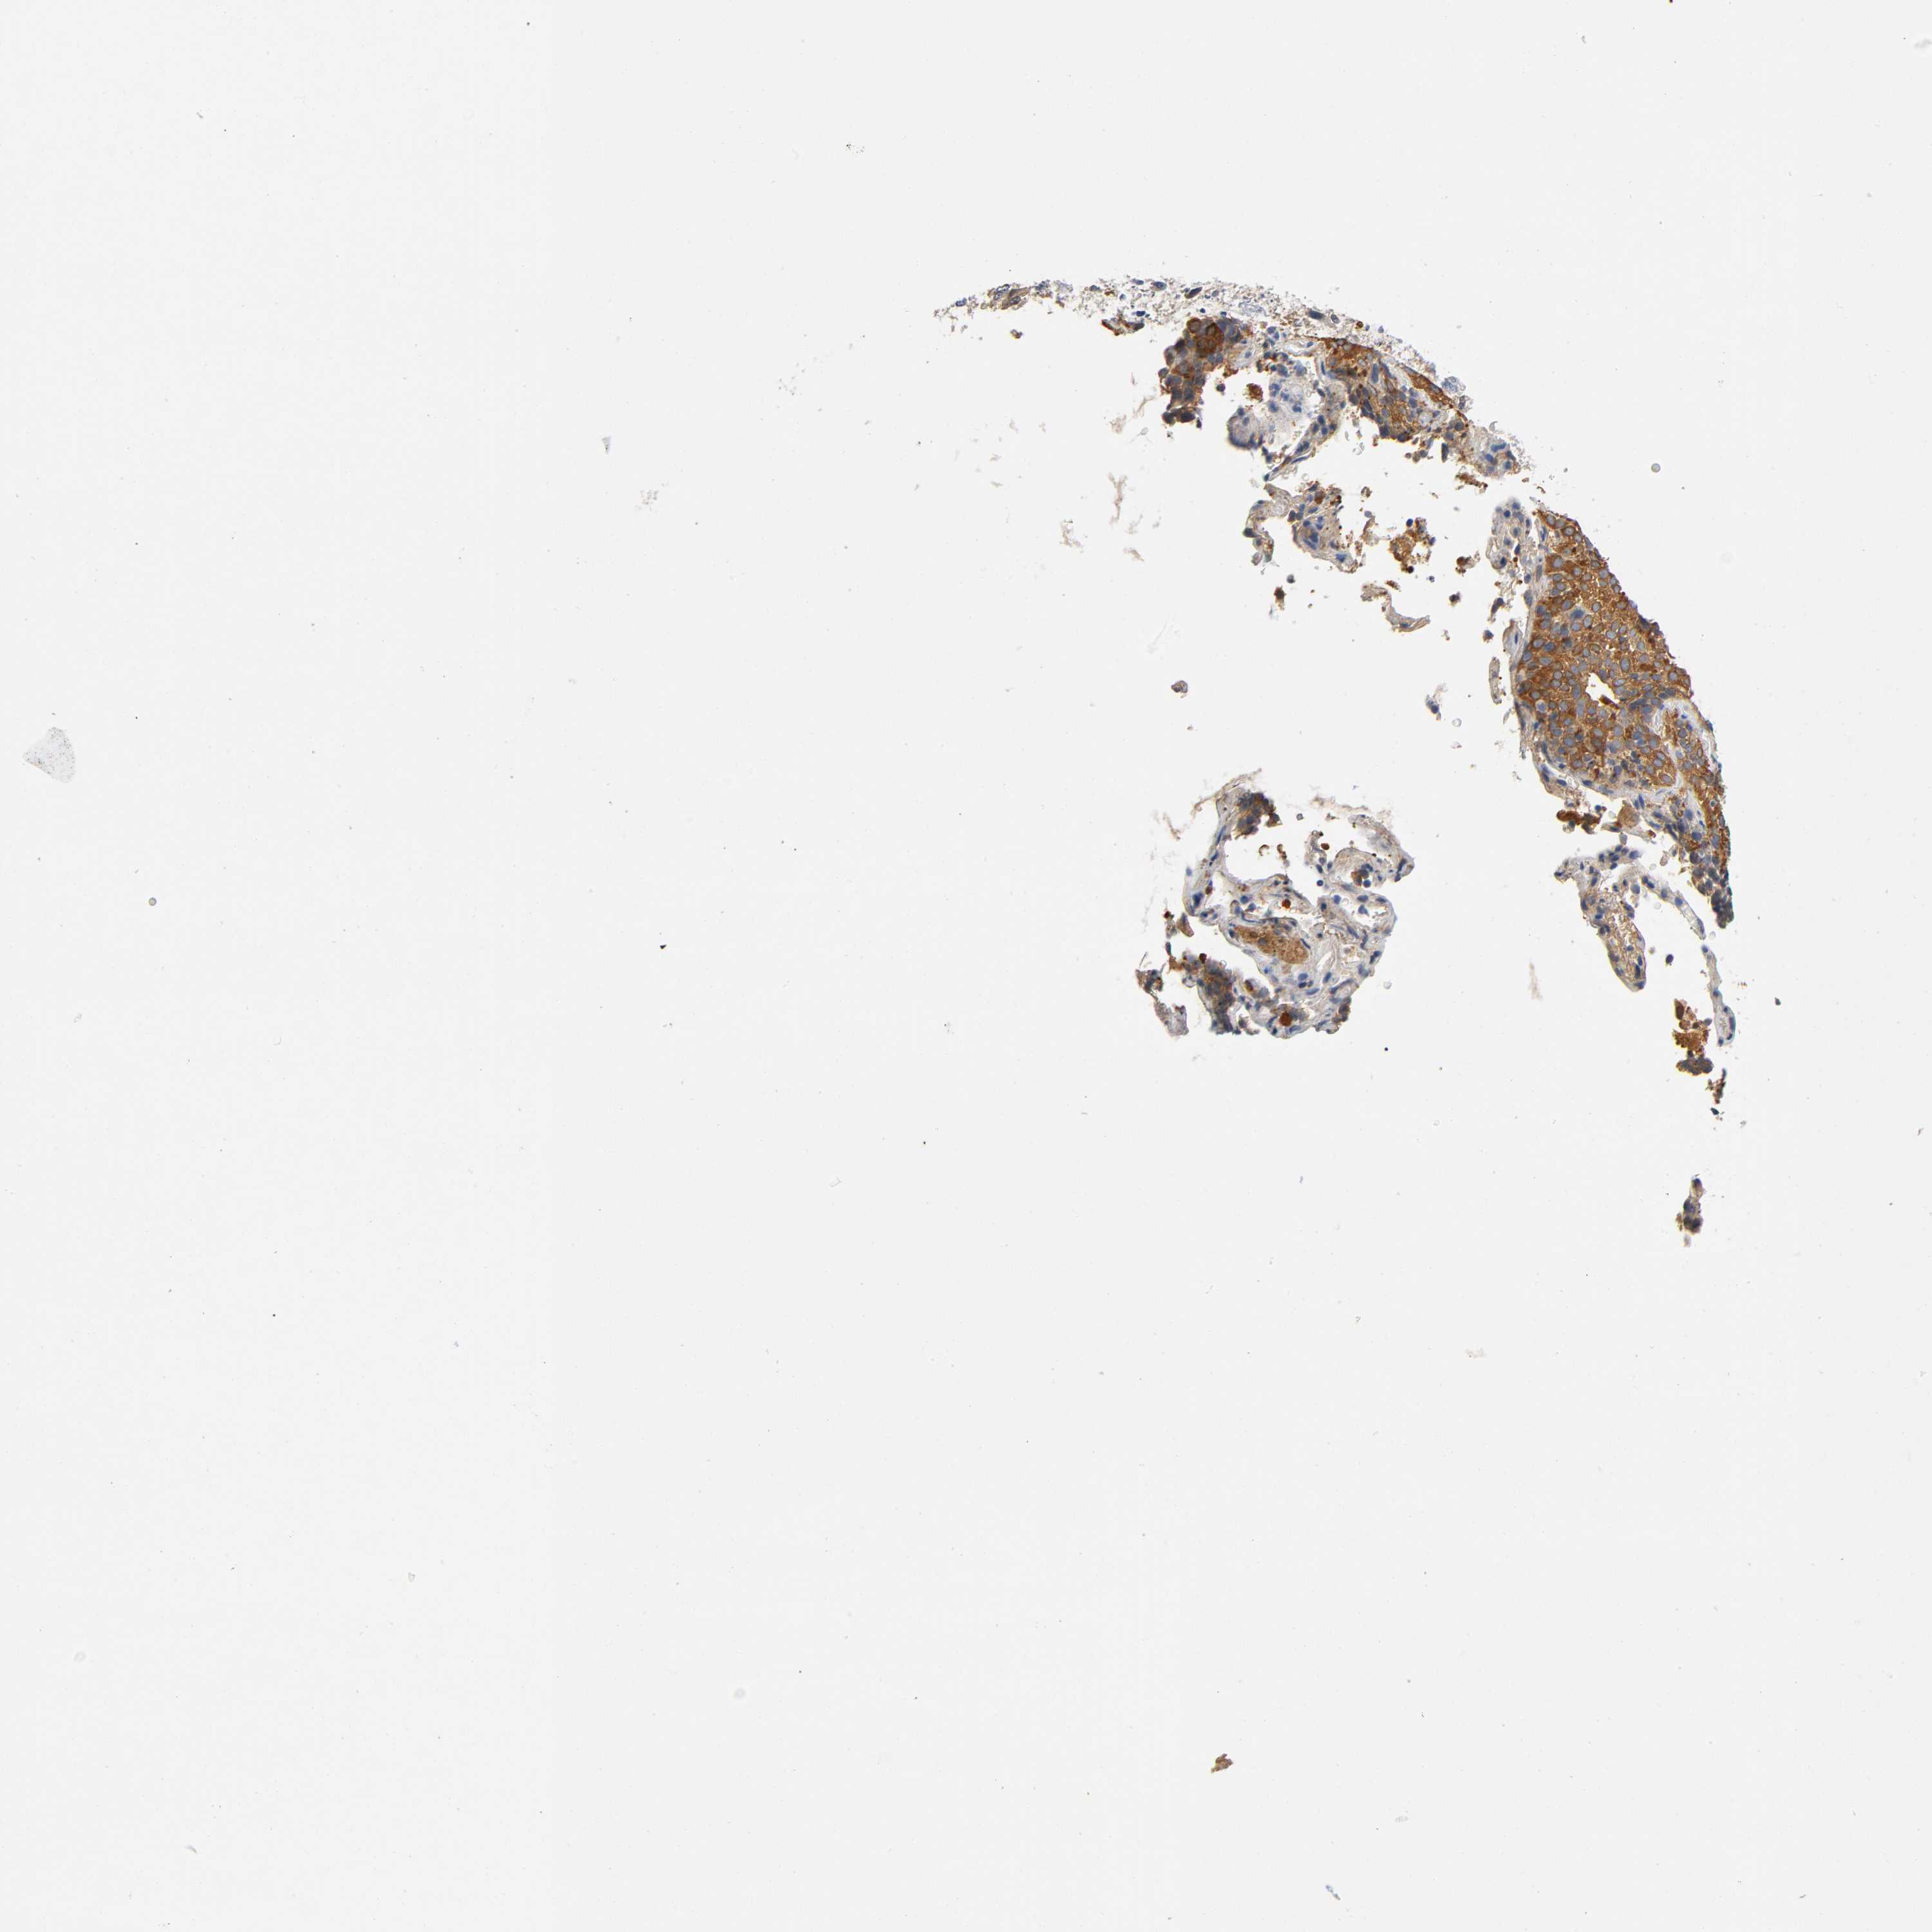

LUNG ADENOCARCINOMA (VALIDATION) - Interactive survival scatter ploti

The Survival Scatter plot shows the clinical status (i.e. dead or alive) for all individuals in the patient cohort, based on the same data that underlies the corresponding Kaplan-Meier plots. Patients that are alive at last time for follow-up are shown in blue and patients who have died during the study are shown in red.

The x-axis shows the expression levels (FPKM) of the investigated gene in the tumor tissue at the time of diagnosis. The y-axis shows the follow-up time after diagnosis (years). Both axes are complimented with kernel density curves demonstrating the data density over the axes. The top density plot shows the expression levels (FPKM) distribution among dead (red) and alive patients (blue). The right density plot shows the data density of the survived years of dead patients with high and low expression levels respectively, stratified using the cutoff indicated by the vertical dashed line through the Survival Scatter plot. This cutoff is automatically defined based on the FPKM cutoff that minimizes the p-score. The cutoff can be changed by dragging the vertical line or by entering a cutoff value in the square labeled "Current cut-off".

Under the Survival Scatter plot the p-score landscape (black curve; left axis) is shown together with dead median separation (red curve; right axis). Dead median separation is the difference in median mRNA expression between patients who have died with high and low expression, respectively. It is calculated as follows: median FPKM expression of dead patients with high expression - median FPKM expression of dead patients with low expression. This is intended to aid the user in visually exploring custom cutoffs and the associated p-scores and dead median separation.

Individual patient data is displayed and can be filtered by clicking on one or more of the category buttons on the top of the page. Categories describing expression level and patient information include: high, low, alive, dead, female, male and tumor stages. The scale of the x-axis can be toggled between linear and log-scale by clicking on the "x log" button. Mouse-over function shows TCGA ID, patient information and mRNA expression (FPKM) for each patient.

& Survival analysisi

Kaplan-Meier plots summarize results from analysis of correlation between mRNA expression level and patient survival. Patients were divided based on level of expression into one of the two groups "low" (under cut off) or "high" (over cut off). X-axis shows time for survival (years) and y-axis shows the probability of survival, where 1.0 corresponds to 100 percent.

TNC is not prognostic in Lung Adenocarcinoma (validation)

Best expression cut offi

Based on the FPKM value of each gene, patients were classified into two groups and association between prognosis (survival) and gene expression (FPKM) was examined. The best expression cut-off refers the FPKM value that yields maximal difference with regard to survival between the two groups at the lowest log-rank P-value. Best expression cut-off was selected based on survival analysis .

When clicking on this number, the vertical dashed line indicating cut-off, the interactive survival plot, and the Kaplan-Meier curve will be adjusted to show results based on the best expression cut-off.

: 37.95

Average pTPM 92.5

Number of samples 105